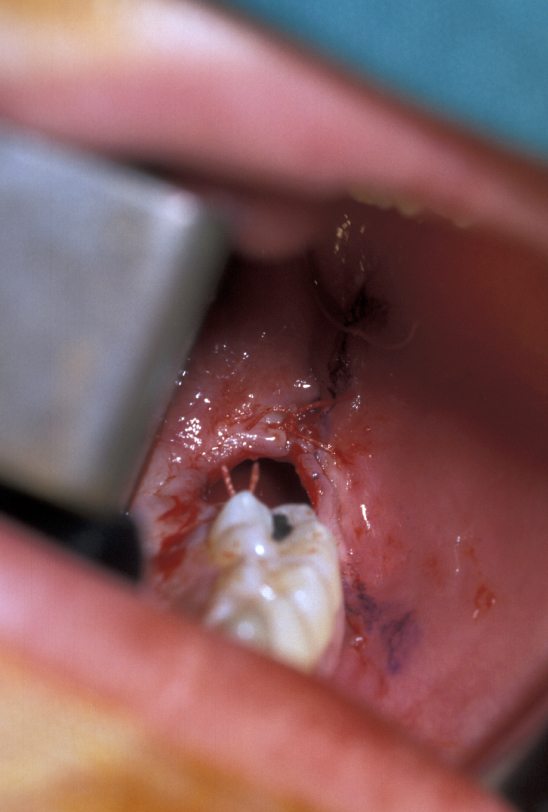

- Lingual Flap – some authorities do not raise a lingual flap at all. The popularity of this approach was from the days when accurate very high-speed surgical drills were not available and the ‘lingual split bone’ technique was popular in the UK and areas influenced by UK training. Their argument is that it is the process of actually raising the flap that causes injury to the lingual nerve. On the other hand, it is argued that the nerve is at risk from direct trauma from the burr/chisel if it is not retracted. Again, if used, the flap is raised by subperiosteal dissection. Here it is important not to ‘bow-string’ the nerve over the retractor (usually a Howarth’s elevator; Figure 1), but to widely undermine the lingual periosteum to allow the tissues to lie passively and use a wide subperiosteally placed retractor. The elevation of a small cuff of distal attached mucosa is designed for visibility, not for ‘lingual nerve protection’ and is not associated with an increase in morbidity (Figure 5).

- Palatally placed canines - open eruption can also be used in the treatment of palatally ectopic canines, especially when they are relatively superficial. As the palatal mucosa is all keratinized, the problem of ensuring that the tooth erupts through here is to ensure adequate crown is exposed to ensure that there is no chance of the crown becoming recovered during the healing phase. If necessary, a bracket can be attached at the time of surgery in the same manner as for closed eruption. Care must be taken to ensure that the cementum is not damaged during surgery and that keratinized mucosa is left overlying the cementum - enamel junction. Interestingly even if large areas of bone are left denuded after surgery healing is usually excellent and uneventful. Packs can be placed over the exposed tooth to aid haemostasis, comfort and to prevent the tooth becoming covered again. This has historically involved the placing of ribbon gauze soaked in varnish and secured in place with mattress type sutures. Periodontal dressing can also be used. The pack should be removed after 7 to 14 days, from when on vigorous oral hygiene measures are vital to encourage healing, prevent gingival overgrowth and encourage eruption (Figure 19 and Figure 20).